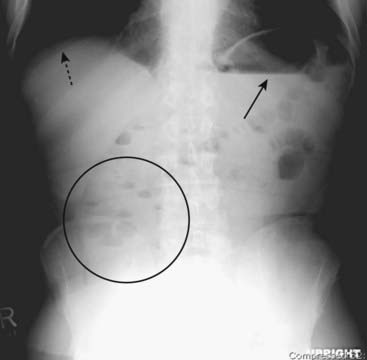

Figure 13-4 Appearance of stool.

Stool is recognizable by the multiple, small bubbles of gas present within a semisolid-appearing soft tissue density (white circle). Stool marks the location of the large bowel and can help in identification of individual loops of bowel on conventional radiographs. This patient has a markedly dilated sigmoid colon from chronic constipation.

Figure 13-5 Aerophagia.

Virtually all bowel gas comes from swallowed air. Swallowing large quantities of air may produce a picture called aerophagia, characterized by numerous polygonal-shaped, air-containing loops of bowel, none of which is dilated (white circle).